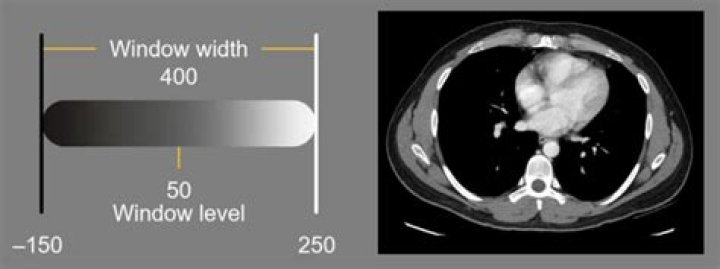

(a) Standard window setting for soft tissue or brain is approximately 60-80HU width and 40HU level (virtual hard copy). (b, c) Use of nonstandard, variable soft copy, narrow window and level settings showed more conspicuous findings of early ishcaemic changes (arrows).Click to see full answer. Likewise, people ask, what is window level in radiology?Windowing, also known as grey-level mapping, contrast stretching, histogram modification or contrast enhancement is the process in which the CT image greyscale component of an image is manipulated via the CT numbers; doing this will change the appearance of the picture to highlight particular structures.Beside above, what does window width control in radiography? In the figure below, the window width (W) determines the range of pixel values that will be incorporated into the display width. Increasing W will reduce display contrast (see figure) whereas decreasing the W increases the brightness interval between two consecutive pixel values. Additionally, what is window width and window level in CT? CT numbers, window width and window level. Window width The window width (WW) as the name suggests is the measure of the range of CT numbers that an image contains. That is range of CT numbers displayed in the CT image. A wider window width (2000 HU), therefore, will display a wider range of CT numbers.What does a Hounsfield unit measure?Definition/Introduction. The Hounsfield unit (HU) is a relative quantitative measurement of radio density used by radiologists in the interpretation of computed tomography (CT) images. The absorption/attenuation coefficient of radiation within a tissue is used during CT reconstruction to produce a grayscale image.